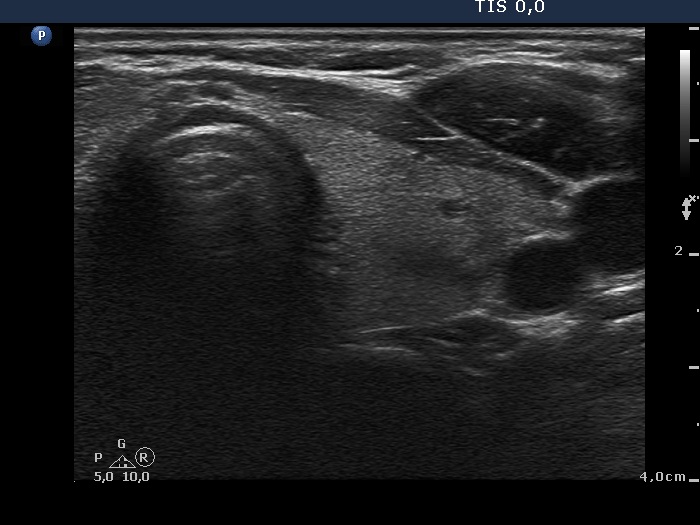

Subacute granulomatous thyroiditis - case 1777 (ultrasonographic picture 7)

Left lobe, transverse view. There is a small minimally-moderately hypoechogenic lesion in the dorsal part of the lobe.